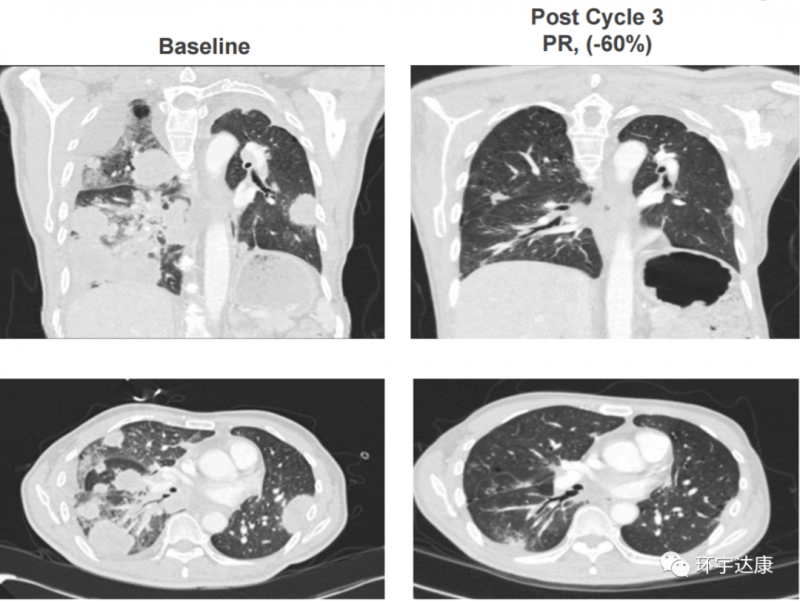

比如这位53岁的男性非小细胞肺癌患者,已经接受了数不清的化疗和免疫治疗,但是病情还是进展了,大家可以很清楚的看到他的双肺填满了肿瘤,属于非常晚期的难治性患者,在接受Adagrasib(MRTX849)联合TNO-155治疗一个周期后,颈部的肿块变平,他已经不再需要吸氧和轮椅,3个周期后,肿瘤就奇迹般的开始缩小了,影像学检查证实肿瘤减少了60%!